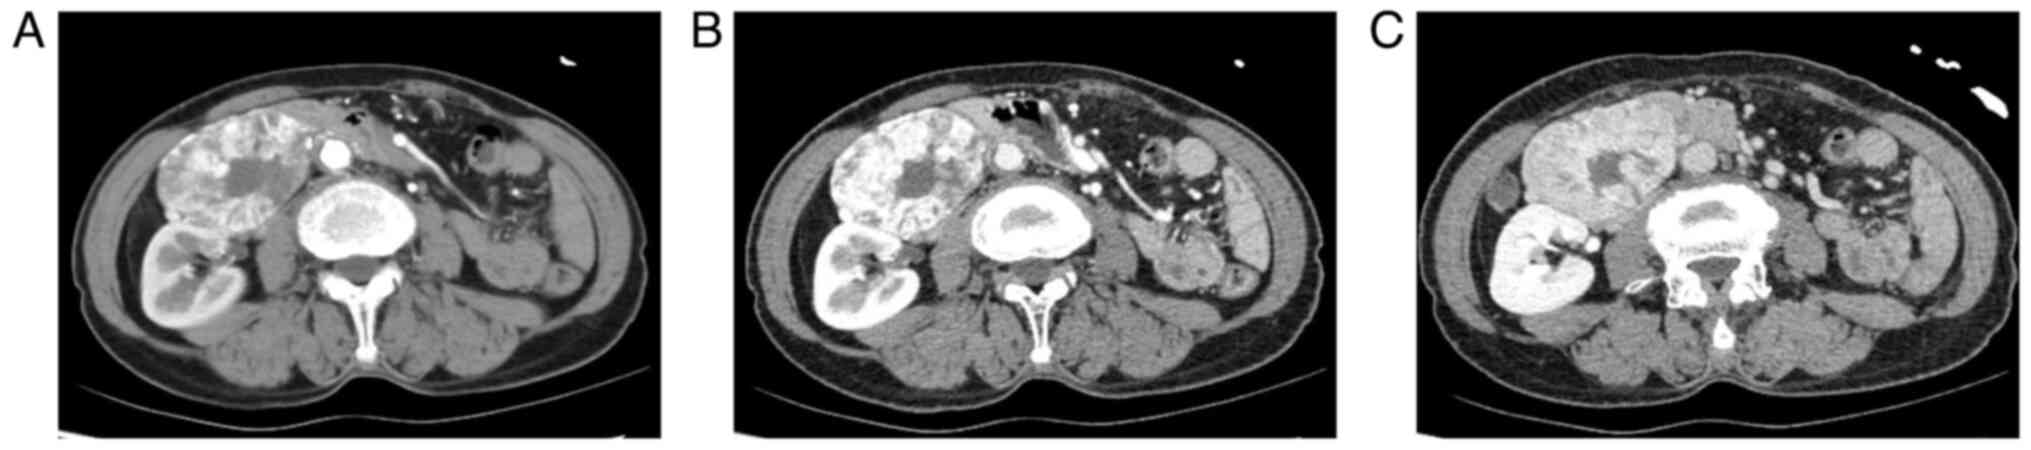

After admission, the patient underwent relevant examinations. Abnormalities were not found in routine blood and biochemical examinations. Other laboratory examinations showed that the level of carcinoembryonic antigen was 7.33 ng/ml (reference value 0-3.4 ng/ml), aldosterone was 52.81 pg/ml (reference value 70-300), methoxyepinephrine was 265.7 pg/ml (reference value 0-145 pg/ml) and norepinephrine was 212.8 pg/ml (reference value 217-1109 pg/ml). On a CT scan of the whole abdomen, a mass-like soft tissue shadow was seen in the lower part of the gallbladder fossa with a clear boundary, measuring ~6.5x5.4x6.6 cm. A low-density area and punctate high-density shadow were seen in the mass against the adjacent tissue, and the partial lesions were close to the intestinal tract. (Fig. 1) On whole abdominal CT enhancement, irregular masses of soft tissue with a clear boundary were seen in the front of the kidney on the right abdomen, and the size was ~6.5x5.4x6.6 cm. On the contrast-enhanced CT scan, the lesions were obviously enhanced inhomogeneously, and there were low-density areas and punctate high-density shadows in the lesions without enhancement. Large vessels were observed in the inside and edge of the lesion, which pushed against the descending and horizontal parts of the duodenum. The anterior margin of the right kidney, the head of the pancreas and the uncinate process were compressed, and the systems of the pancreatic duct and bile duct were slightly dilated.

Figure 1

Preoperative contrast-enhanced CT. (A) Arterial phase, (B) venous phase and (C) delayed phase.